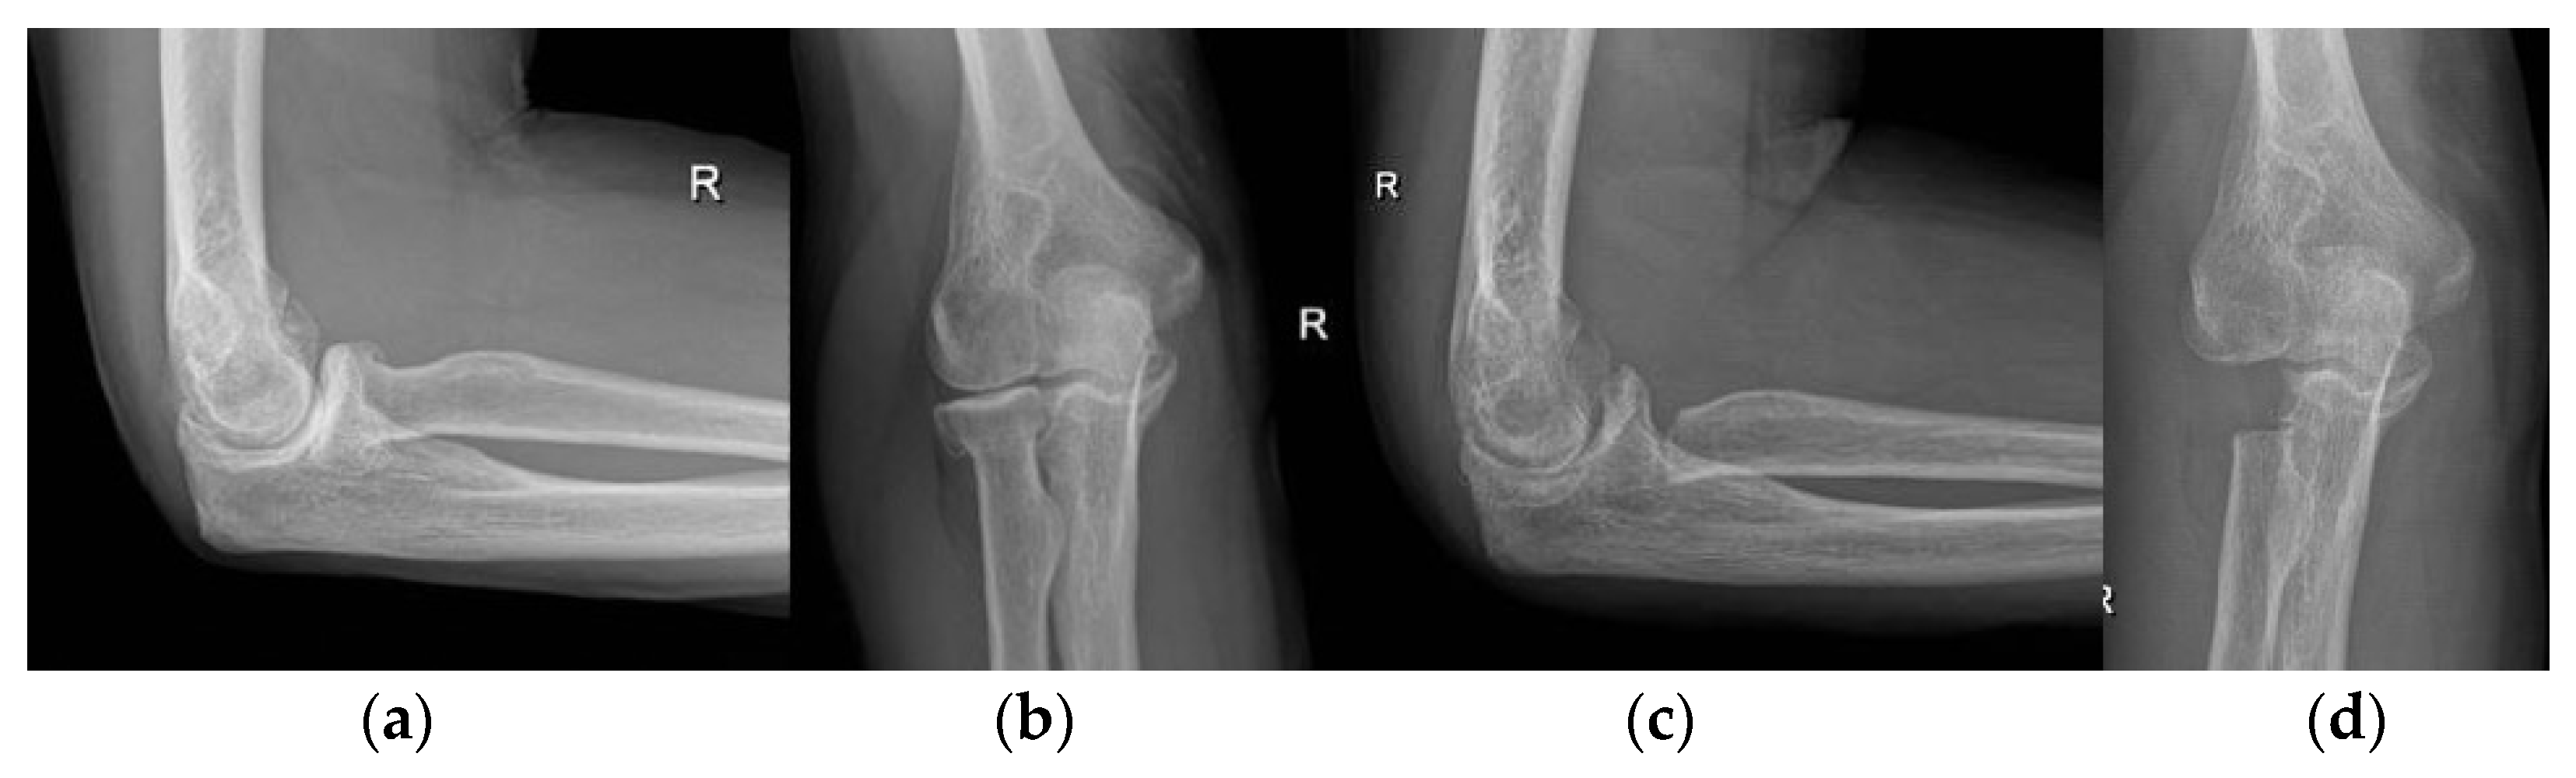

3.3. Elbow

- Martinez-Catalan, N.; Sanchez-Sotelo, J. Primary Elbow Osteoarthritis: Evaluation and Management. J. Clin. Orthop. Trauma 2021, 19, 67–74. [Google Scholar] [CrossRef]

- Kwak, J.-M.; Jeon, I.-H. Surgical Management for Primary Osteoarthritis of the Elbow. J. Orthop. Surg. Hong Kong 2021, 29, 2309499020988174. [Google Scholar] [CrossRef]

- Baghdadi, Y.M.K.; Morrey, B.F.; Sanchez-Sotelo, J. Anconeus Interposition Arthroplasty: Mid- to Long-Term Results. Clin. Orthop. 2014, 472, 2151–2161. [Google Scholar] [CrossRef]